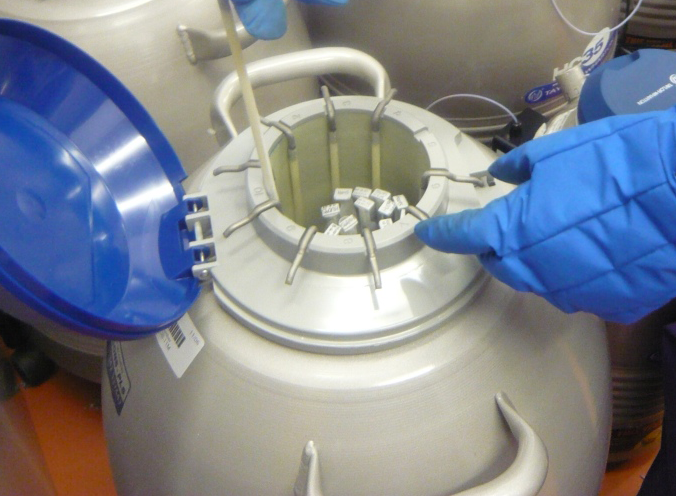

“Щом веднъж Стептоу и Едуардс успяват да оплодят яйцеклетка, те много бързо разбират, че трябва да ограничат броя получени ембриони за трансфер, за да намалят вероятността за многоплодна бременност”, обяснява Макнами. “Развитието на крио технологиите през 80те години довело до трансфер само на 1-2 ембриона и замразяването на останалите за бъдеща употреба. По този начин се спестява повторно извличане на яйцеклетки.”

Замразяване на ембриони за последващ трансфер